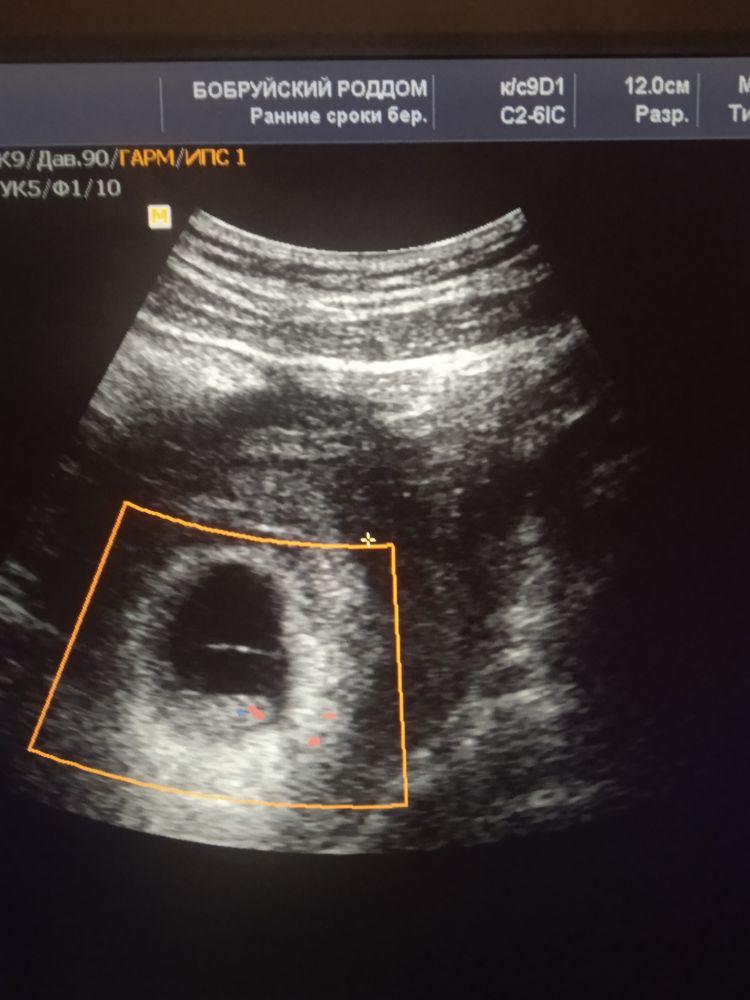

На узи нам не сказали, кто там, судя по многочисленным узи правильно ли я понимаю, что это и есть тот самый бугорок, который показывает девочку? 😁

На узи нам не сказали, кто там, судя по многочисленным узи правильно ли я понимаю, что это и есть тот самый бугорок, который показывает девочку? 😁